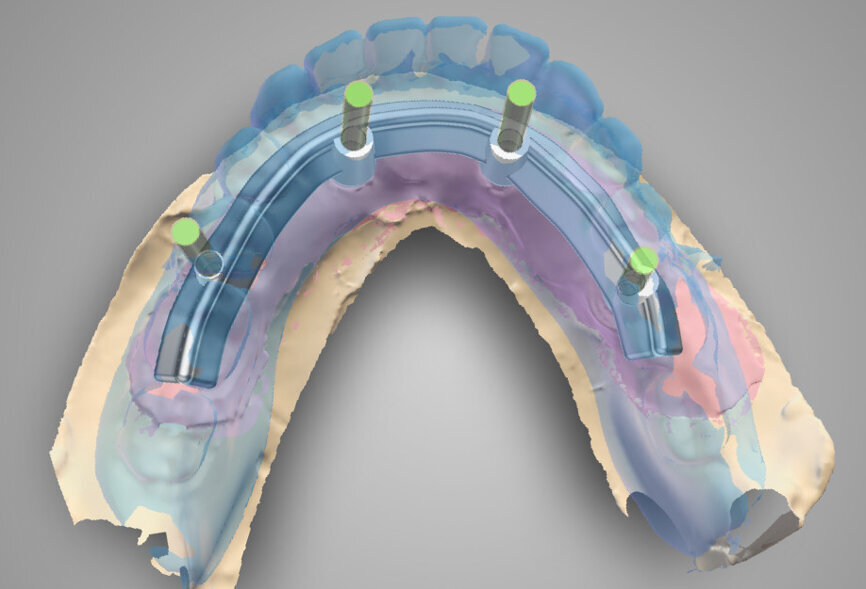

The planning included several steps. First, the hopeless teeth in the mandible were to be extracted, followed by delivery of a complete immediate denture, as they did not offer any stable support for a surgical guide. Six weeks later, owing to the lack of keratinised tissue in the premolar regions, apical repositioning and a free gingival graft were performed (Fig. 2). After 1.5 months, the denture was relined with a mixture of barium sulphate and resin, transforming the denture into a radiographic stent (Fig. 3). Another CT scan was recorded with the stent in the mouth (Fig. 4). The stone cast of the stent was poured (Fig. 5), giving us the actual clinical picture of the mucosa, and both cast and stent were scanned to obtain their STL files. Using the coDiagnostiX planning software, the radiopaque saddle of the stent and the STL scan were matched, which also allowed the stent to be matched with the cast as positive and negative, thus, giving us the soft-tissue volume. Implants were planned in a prosthetically driven manner at sites #34, 32, 42 and 44, with corresponding screw-retained abutments (Fig. 6).

Because of an open-flap procedure owing to the lack of keratinised tissue and the placement of long implants (all Straumann BLT Roxolid, SLA implants; 4.1 × 12.0 mm), it was decided to make two surgical guides: first, a mucosa-supported guide only for drilling the template fixation pins (Straumann; Fig. 7); and second, a pin-supported guide for fully guided implant placement (Fig. 8).